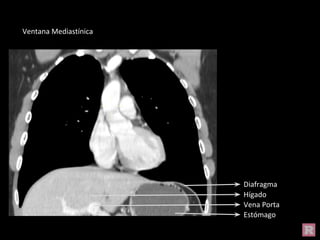

Ventana Mediastínica

Diafragma

Estómago

Hígado

Vena Porta